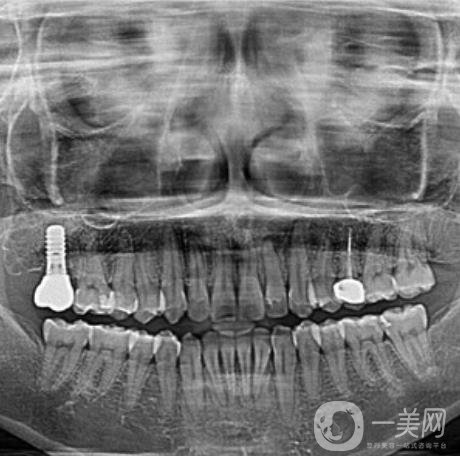

三、天津愛齒口腔種植牙案例

我掉的那顆牙齒是因為我咬東西的時候不小心要掉了一半,后來牙齒松動直接就掉了。估計大家可能還會嘲笑我怎么這么沒出息,吃東西都可以把自己的牙齒給割掉,其實我想說的是實在是太寸了,真的沒有想到我的牙齒會這么脆弱。有一個牙洞實在是太別扭了,到口腔醫(yī)院讓醫(yī)生給我看了一下,說是可以做種植牙這個手術來補上之前那個牙洞。醫(yī)生簡單的和我說了一下,種植牙是一個怎么樣的手術,以及手術的大概過程和術后修復。

做完種植牙已經四個半月的時間了?,F(xiàn)在我的那顆牙齒早就已經種好了。在種好了之后我特別小心的使用著,可牙齒醫(yī)生還告訴我這顆牙齒是特別堅固的,比我自己長的那些牙齒還要兼顧,讓我放心好了,現(xiàn)在的我吃東西一切都恢復了正常。我感覺*近幾天都讓我長胖了,畢竟每天胡吃海塞的。